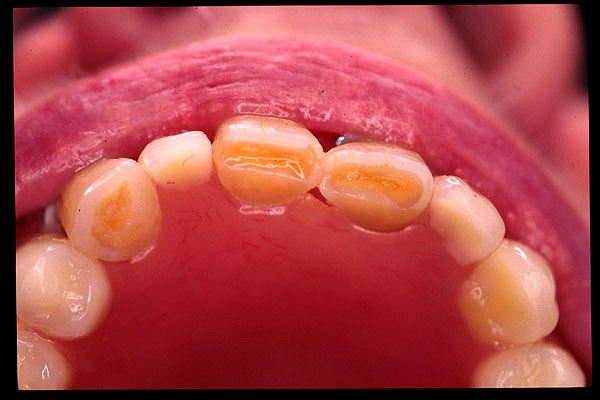

CM Desgaste por bruxismo